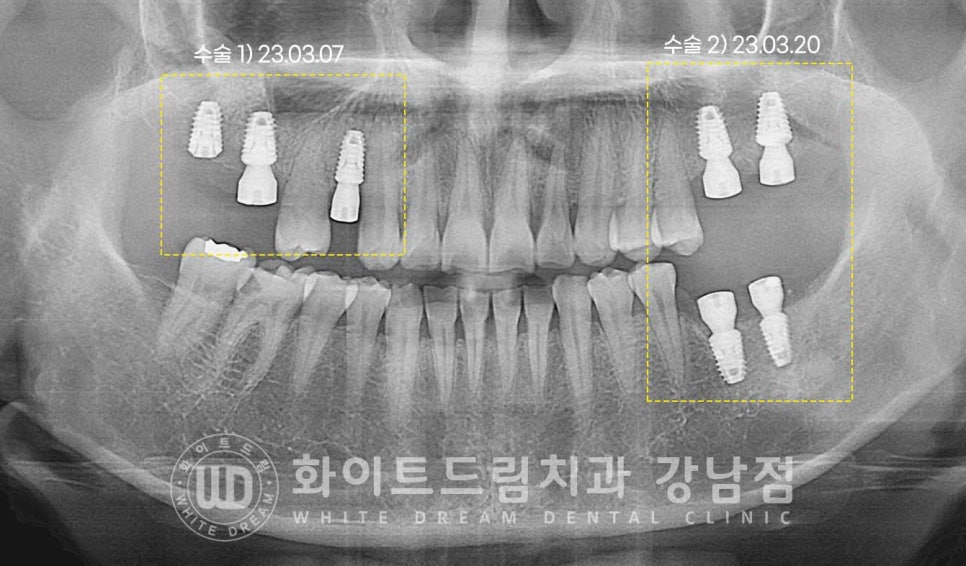

▲ 상악동 거상술 & 임플란트 수술 후 (23.03.07)

2회로 나누어 임플란트 식립을 진행하였습니다.

오른쪽 상악 : 23.03.07 / 왼쪽 상, 하악 : 23.03.20

많은 양의 뼈이식이 동반되었기에

충분히 임플란트가 유착될 수 있도록 회복 기간을 넉넉히 잡기로 했습니다.

환자분은 수술 후 5개월의 회복 기간을 가진 후

임플란트 보철 제작 & 세팅에 들어가게 되었습니다.